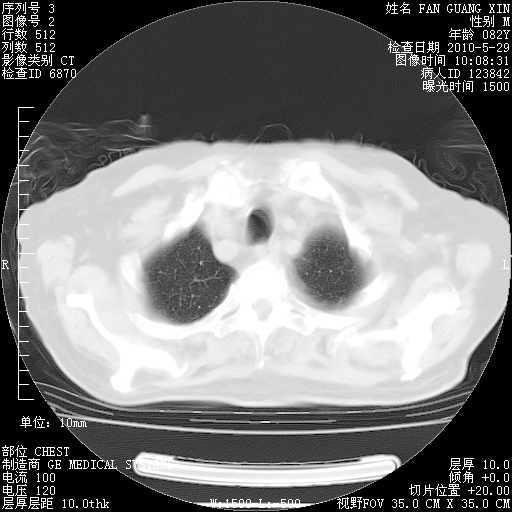

治疗3周后的肺部CT纵隔窗

再治疗10天后的肺部CT

再治疗10天后的肺部CT 纵膈窗

阅读此次胸部CT,肺间质渗出性改变较入院时有吸收。目前从体温、白细胞、中性分叶明显增高,肯定存在细菌感染(发生医院感染哦,若无消化道及泌尿系统等感染的依据,肺部感染可能大)。若你院头孢哌酮舒巴坦钠耐药率较高,同意你的方案,若48小时体温仍高,可考虑使用碳青霉稀类抗菌药物,同时可予超声雾化、注意滴数时加大液体量。白蛋白33.30g/L较低哦,需加强营养等支持治疗。